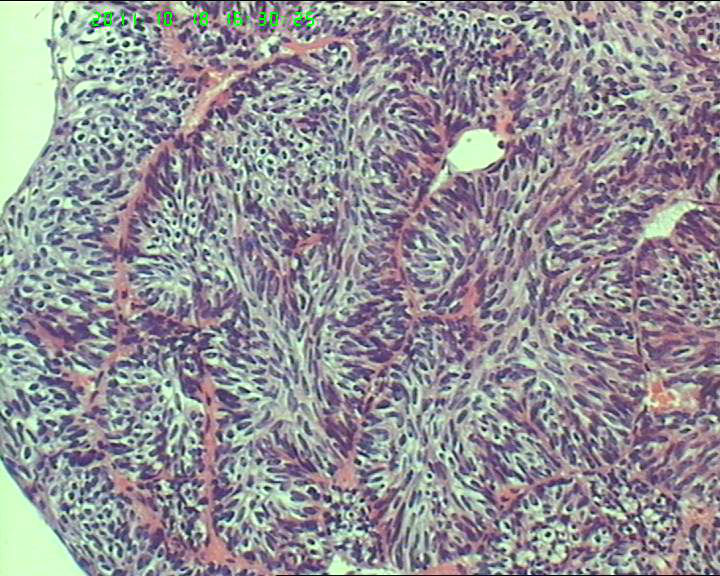

70岁女性体检发现膀胱肿物,是癌吗?

膀胱后壁一2*1cm大小肿物